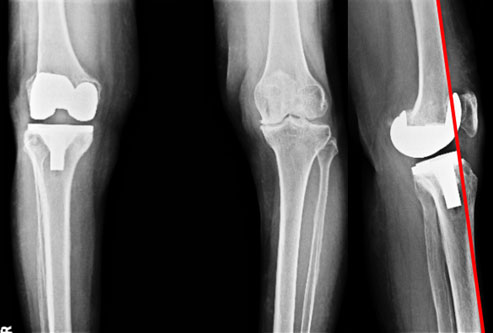

The x-ray pictures after the surgery. A cemented PFC sigma total knee replacement (involves a metallic component sitting on the lower femur, a metallic tibial tray & a polyethylene insert in between) was done. The patella (knee cap) was not replaced as the articular surface didn’t show much damage. The skin staples are still seen. The picture on the right shows the reduction of flexion deformity, but not the complete resolution. That is because only part of the flexion deformity was from the bone, the rest of it was from the soft tissue, which gradually stretch out with exercises.